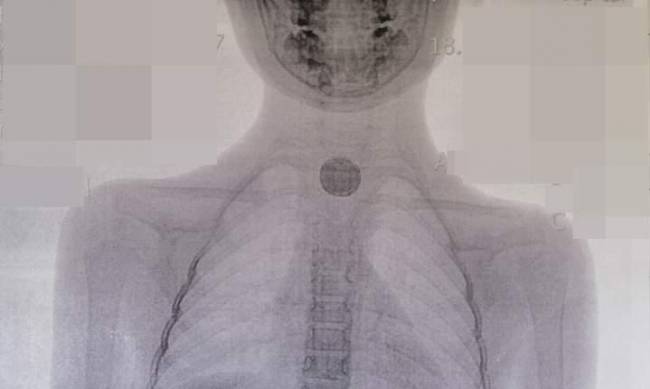

Рентген показал наличие инородного тела в пищеводе. Во время операции стало ясно, что этим инородным телом являлась батарейка округлой формы, размером с 25-копеечную монету. Медики ее достали, но она успела "натворить делов" - внутри пищевода все было черное от ожога и отекшее.